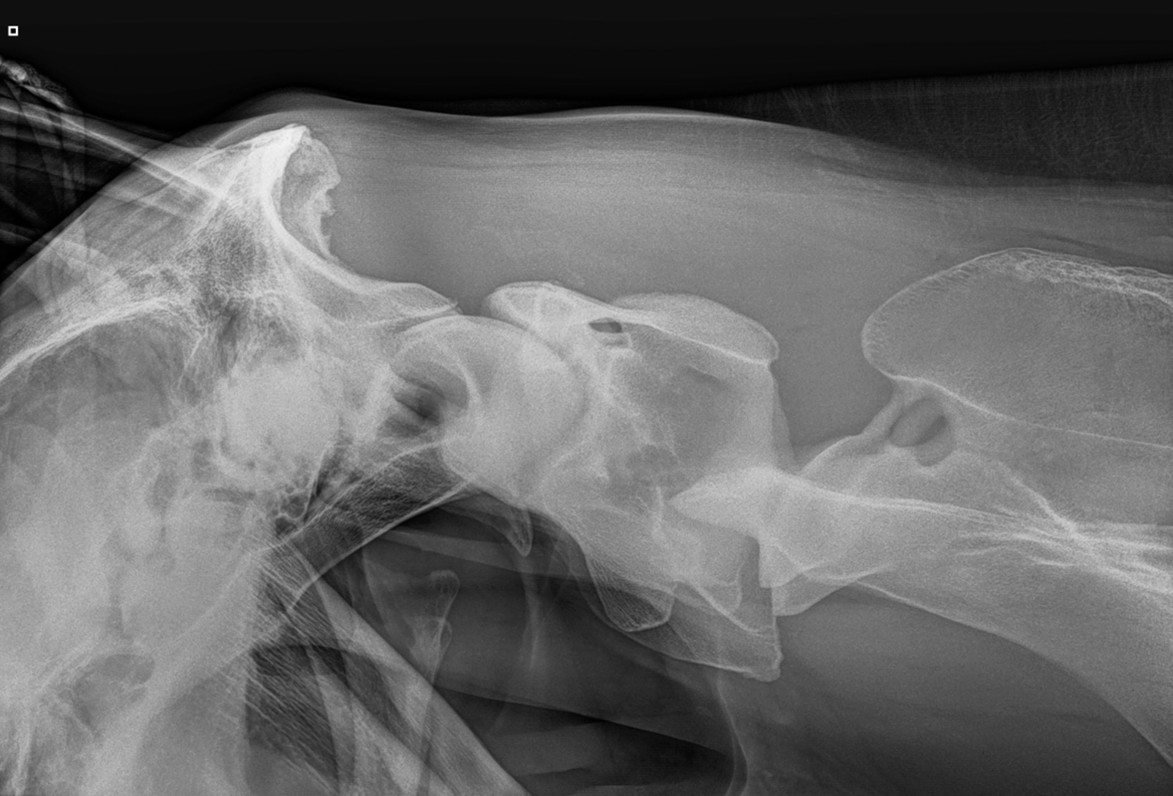

Laterolaterale (LL) projectie van de craniale hals: